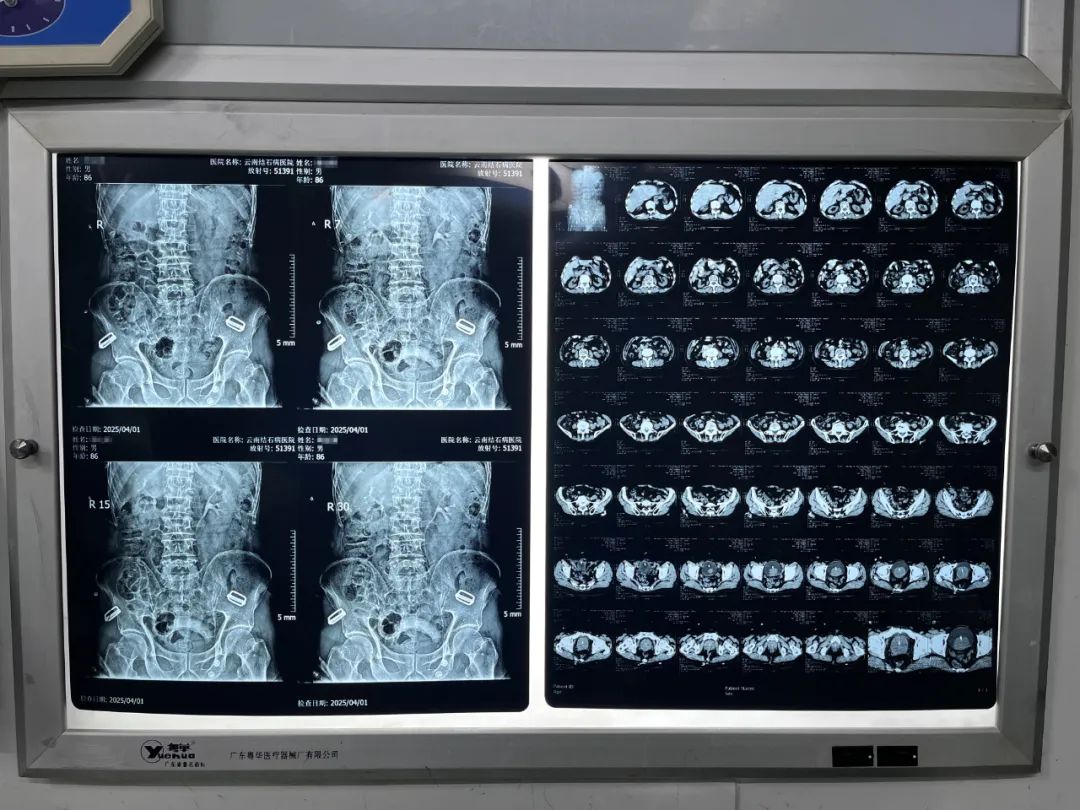

图片来源网络,侵权联系删除